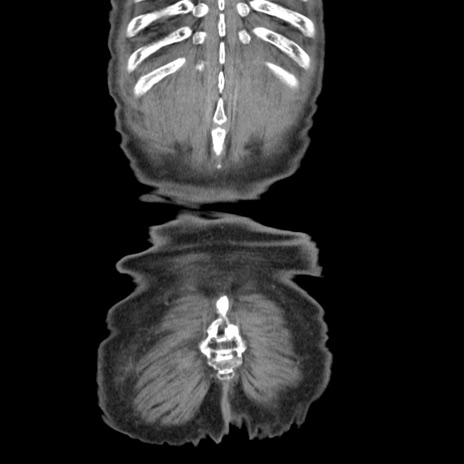

横断像

矢状断像